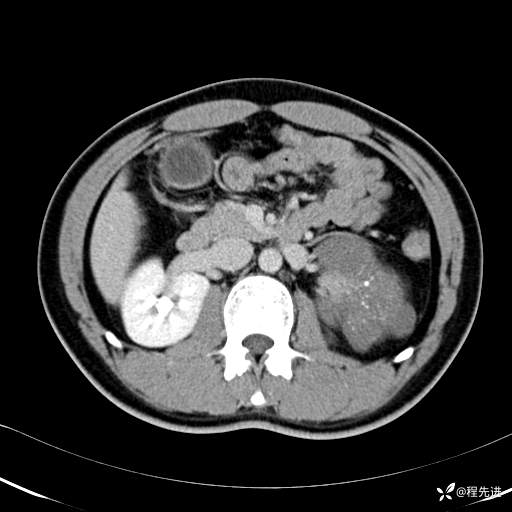

CT平扫:(CT值:平扫,27HU,动脉期,27HU,门静脉期,31HU,平衡期,32HU)

门静脉期: